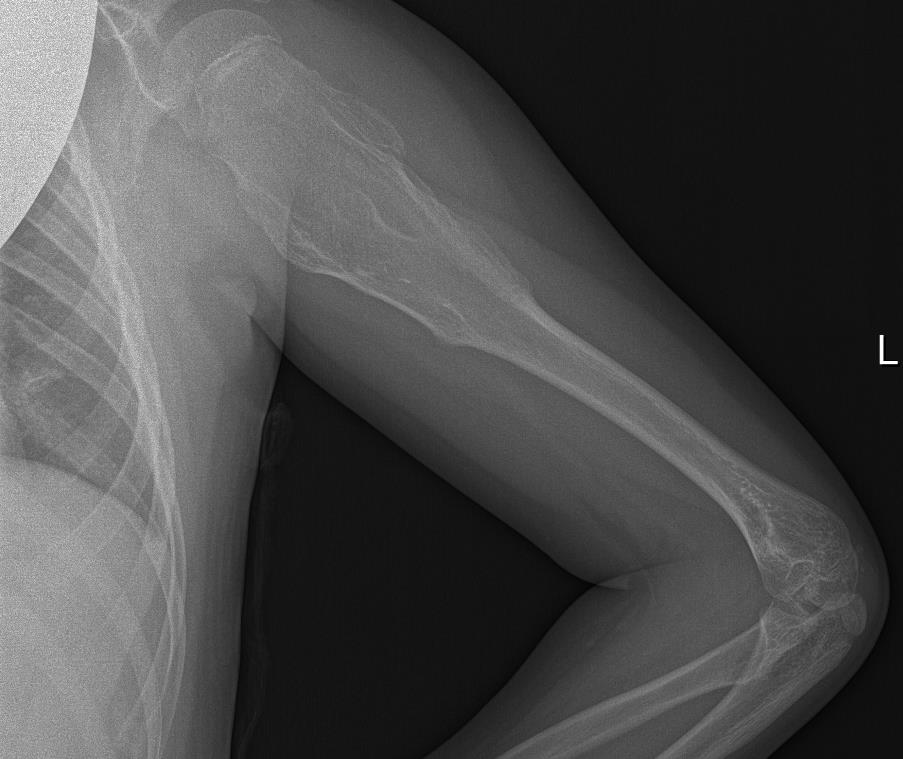

Radiografía de Miembro superior izquierdo: Se visualiza lesión lítica metafiso-diafisaria en húmero izquierdo expansiva con excrecencias óseas y margen estrecho con hueso sano.

Juicio clínico: Exostosis múltiple chereditaria. Osteocondromas múltiples (ORPHA 321) de novo.

Diagnóstico diferencial: Osteocondroma plano vs Displasia fibrosa.